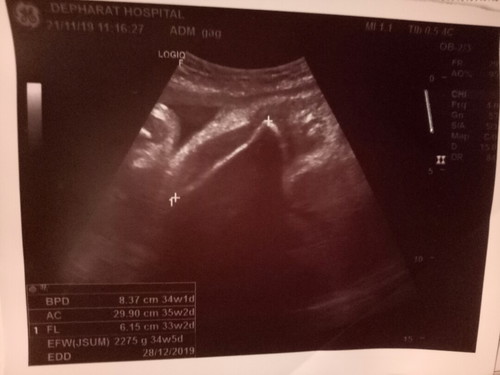

พึ่งสังเกตรูปอัลตร้าซาวด์ค่ะ ดูไม่ออกเลยว่าส่วนไหนเป็นส่วนไหน ด้านซ้ายเหมือนหน้าคนเลย ดูรูปแล้วก็แอบกลัวค่ะ หรือเราคิดไปเองก็ไม่รุ้ เพราะคุณหมอก็บอกแค่น้องกลับหัวแล้ว น้ำหนักเท่าไหร่ เพศอะไร แค่นั้น กลัวน้องไม่สมบูรณ์ค่ะ?

อันนี้น่าจะเป็นภาพลากเส้นกระดูกขาค่ะ

น้ำหนัก2275กรัมค่ะเเม่ เพศไม่เห้นค่ะ